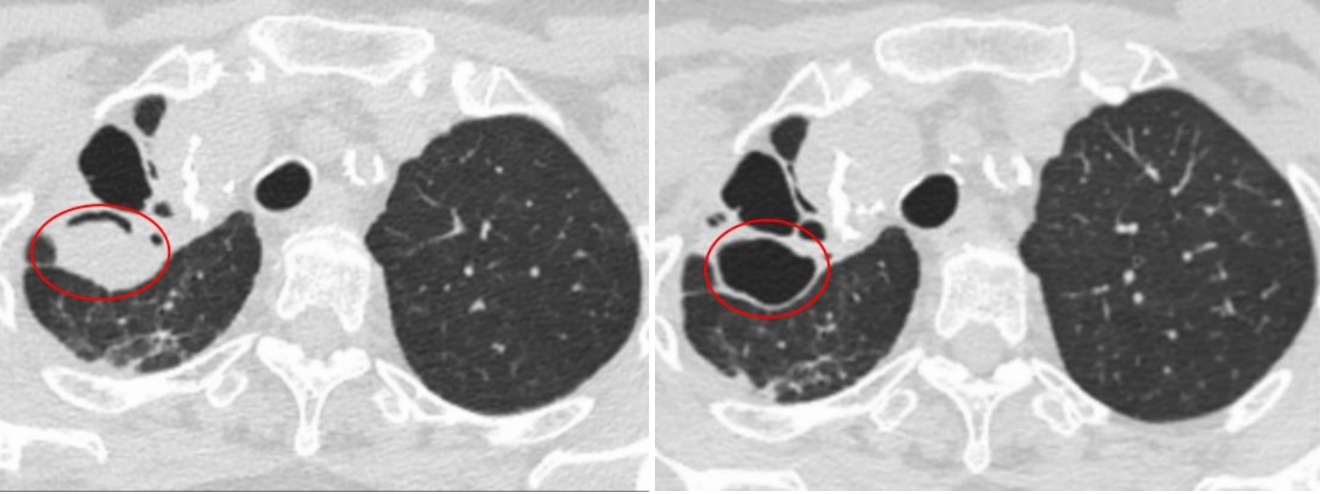

八旬老太久咳不愈是为什么?张言斌带领科室团队化身肺部“侦探”,推测曾婆婆可能存在右上肺空洞继发曲菌球感染。为了进一步查明咯血病因,张言斌为曾婆婆进行了支气管镜检查。聚光灯下,张言斌在曾婆婆肺部右上叶后段扩张及空洞内有了“新发现”!病理报告敲定了最后的诊断:右上肺空洞内烟曲霉菌感染,导致了慢性空洞性肺曲霉病。

4月18日,在张言斌和呼吸与危重症医学科副主任钟海波带领下,团队为曾婆婆进行了第1次支气管镜介入治疗。一根细长的导管缓缓进入患者呼吸道,通过屏幕,医生们能够清晰地看到曲霉菌球的轮廓。专家们小心翼翼地切除病灶,每一步都精确到毫米级,力求在不伤害周围正常组织的情况下顺利完成了手术。一个小时后,成功将患者空洞内大部分曲霉球清除。

5月10日,曾婆婆再次入院接受第二次支气管镜下治疗,对残留的少许曲菌球进行镜下清除。终于顺利将空洞内曲菌球完全清除干净。术后四天,曾婆婆咳嗽、咳痰症状明显改善,咯血症状消失,病情明显好转顺利出院。